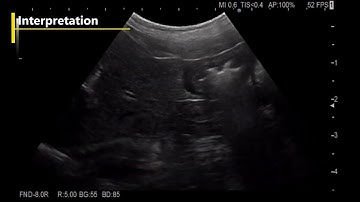

Dochoscopy Duodenum